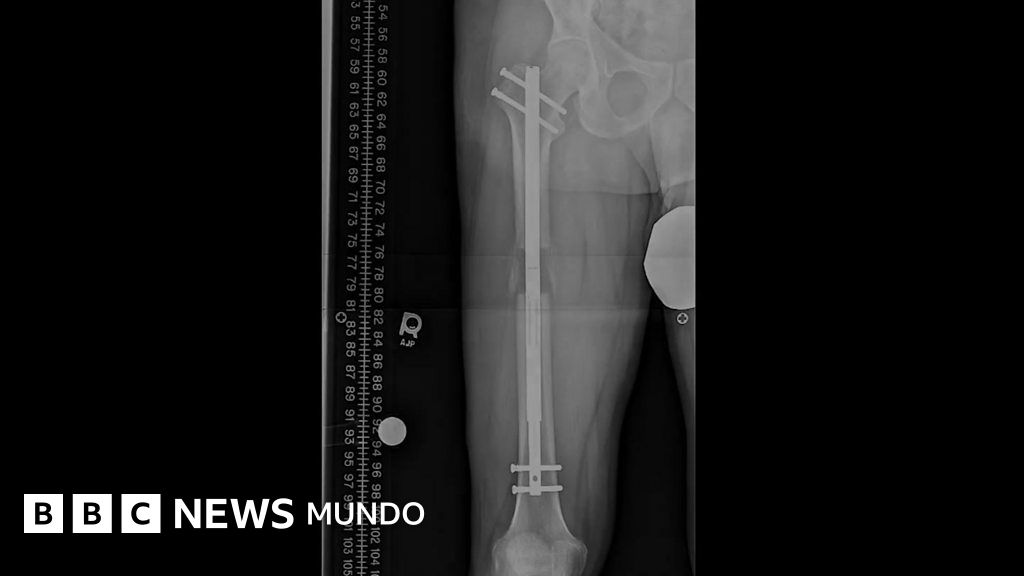

Es una operación larga, dolorosa y costosa. Consiste en romper huesos, normalmente de la pierna, para estirarlos con la ayuda de otra herramienta.